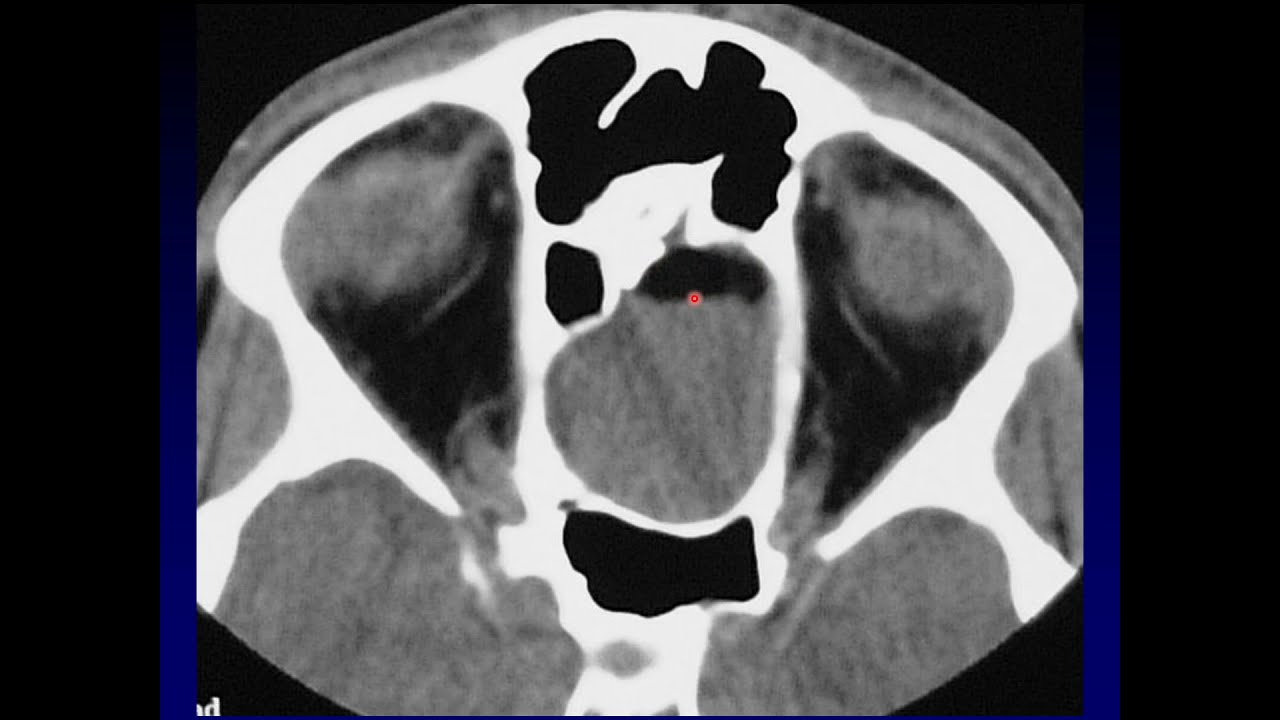

Imaging of the Paranasal Sinuses 4

Part 4 (of 5) covers benign and malignant masses, as well as the differential for an enlarged sinus.